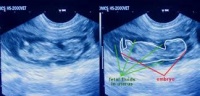

Hembra gestante y cachorro canino

La hembra gestante y el cachorro canino, deben recibir un grupo de cuidados especiales para el logro de una cría saludable, que van, primero, desde las acciones relacionadas con la propia gestación, hasta llegar al feliz nacimiento de los cahorros.